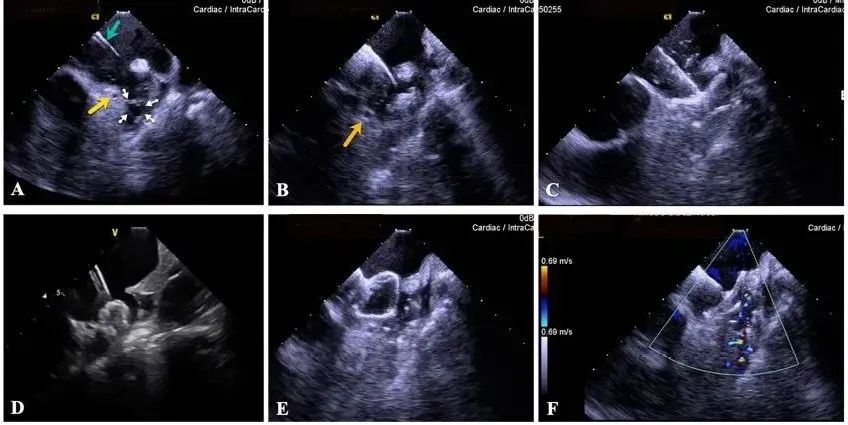

一種與心導(dǎo)管檢查相結(jié)合的超聲心動(dòng)圖診斷新興技術(shù),通過將超聲探頭置于心腔內(nèi)部,發(fā)射并接收超聲信號(hào),來精確獲取心臟解剖結(jié)構(gòu)、心臟血流動(dòng)力學(xué)等信息的實(shí)時(shí)成像。與其他影像技術(shù)相比,ICE技術(shù)具有操作簡單、無輻射、安全性高、手術(shù)效率高、實(shí)用等優(yōu)勢(shì),ICE在很大程度上有望取代經(jīng)食道超聲心動(dòng)圖(TEE),成為電生理和結(jié)構(gòu)性心臟病領(lǐng)域的理想成像方式。

目前ICE技術(shù)已被應(yīng)用于左心耳封堵、房顫射頻消融、二尖瓣成形、房間隔缺損封堵等多種心臟介入手術(shù),應(yīng)用場景主要圍繞心臟電生理、結(jié)構(gòu)性心臟病等領(lǐng)域,目前以電生理應(yīng)用為主。數(shù)據(jù)顯示,我國結(jié)構(gòu)性心臟病介入器械市場規(guī)模已從2017年的4億元增長至2021年的20億元,年復(fù)合增長率達(dá)48.3%;預(yù)計(jì)到2025年,該市場規(guī)模將達(dá)到104億元,可以預(yù)見ICE市場規(guī)模也將同步高速增長,未來市場發(fā)展空間廣闊。

心腔內(nèi)超聲(ICE)技術(shù)壁壘極高,國內(nèi)主要廠商核心部件仍舊為進(jìn)口,集成了超聲和圖像處理最前端技術(shù),包括超聲探頭、線纜、軟件成像算法等,是當(dāng)前內(nèi)窺超聲方向最具挑戰(zhàn)的領(lǐng)域。ICE的應(yīng)用經(jīng)歷了2D平面成像、3D三維立體成像、以及4D的實(shí)時(shí)三維立體成像階段。